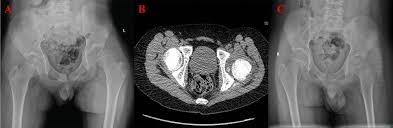

يجب إجراؤه بعد الرد لتقييم:

إجراء CT للورك والحوض لتقييم جودة الرد ووجود شظايا أو كسور مرافقة.